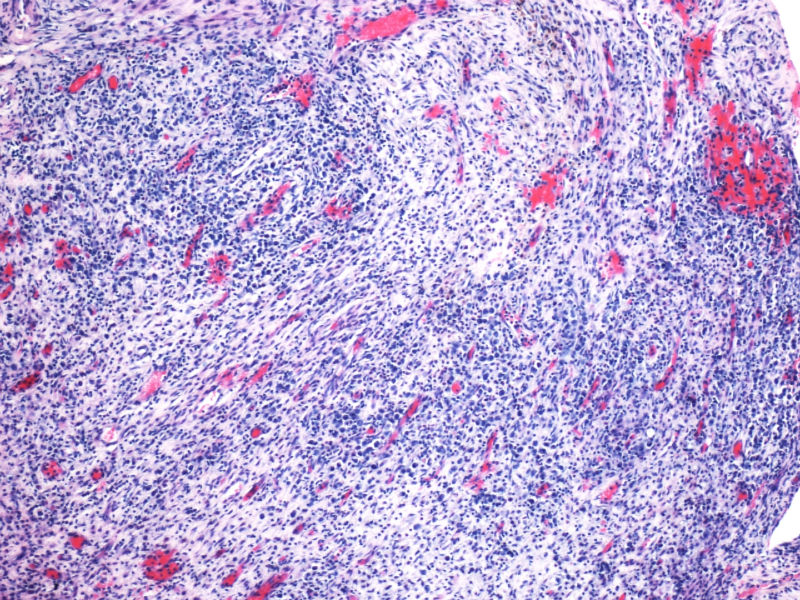

最终诊断为:ALK阳性的间变性大细胞淋巴瘤,淋巴组织细胞变异型。

拿出来的目的:本例始发于骨骼,临床提示脓肿或骨髓瘤,ALK阳性但EMA阴性,细胞毒只有一个标记阳性,本例CD4不阳性。因为CD30和CD15均有非肿瘤细胞阳性的情况,所以对于这个骨骼病例,细胞少而退变,因此最初没有信心诊断,但ALK一般不在非肿瘤细胞内阳性表达,所以最终还是诊断了ALCL。

形态学hallmark 细胞显示不是很清晰,大的肿瘤细胞如果在ALCL和HL之间选择可能不容易,但HL的肿瘤细胞形态学特点的范围比较狭窄,而ALCL可能具有更广泛的形态学范围,细胞大小形态以及典型hallmark cell的多少有时很难确定。如果只看HE,觉得ALCL的可能会安全一点,当然我个人经验不足,可能理解得比较肤浅。

本例CD68的表达也许很重要,HL可以有严重的炎症背景,但背景细胞是否会出现如此明显CD68阳性细胞,还请各位老师教我;而ALCL CD68大概可以阳性。另外就是哪些细胞是肿瘤细胞的问题了,可能未必局限于CD30阳性的大细胞吧。